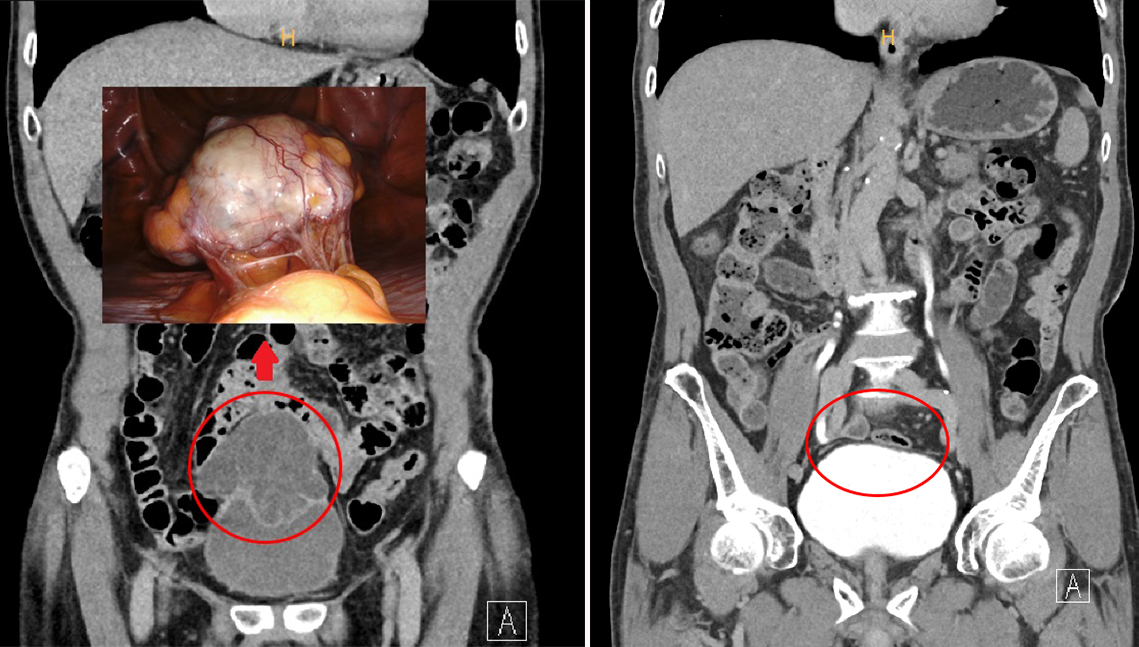

71세 남성 고령 환자에 적합한 고난도 술기 구사, 출혈 및 합병증 줄여 … 작년 3월엔 신장 신우요관 파열수술

이상욱 순천향대 부천병원 비뇨의학과 교수가 다빈치 Xi 로봇수술로 ‘희귀 거대 요관막암’을 제거하는 데 성공했다고 19일 밝혔다. 요관막은 태아 시절 방광과 배꼽 사이를 연결하는 관으로 출생 후에는 섬유끈으로 바뀌어 정중 배꼽 인대가 된다.

환자는 71세 남성으로 8cm 크기의 큰 암 덩어리가 배꼽 직하부 요막관에 자리 잡아 방광까지 침범한 상태였다. 고령인데다가 혈관이 매우 발달해 수술 시 극심한 출혈 위험성이 높고, 해부학적인 파악도 쉽지 않아 고난도 수술이 필요했다.

이에 이상욱 교수는 다빈치 Xi 로봇수술을 택했다. 수술 부위를 3D 영상으로 15배까지 확대해보면서 자유롭게 회전하는 로봇 팔을 이용해 정밀하게 요막관 제거 및 방광 부분 절제술을 시행해 거대 요막관암을 제거했다.

이상욱 교수는 “환자가 고령인 점을 고려해 다른 장기 손상과 통증, 진통제 사용량을 최대한 줄일 수 있는 로봇수술을 시행했다. 기존의 개복 또는 복강경 수술보다 출혈과 합병증이 적어 빠르게 회복할 수 있다는 점에서 고령 환자에게 적합한 수술 방법”이라고 말했다.

이 교수는 지난해 3월에도 교통사고로 한쪽 신장의 신우요관 이행부가 파열된 17세 환자를 국내 최초로 ‘로봇 신우요관문합술’을 통해 치료하는 등 지역 의료계에서 고난도 로봇수술 명의로 명성을 떨치고 있다.